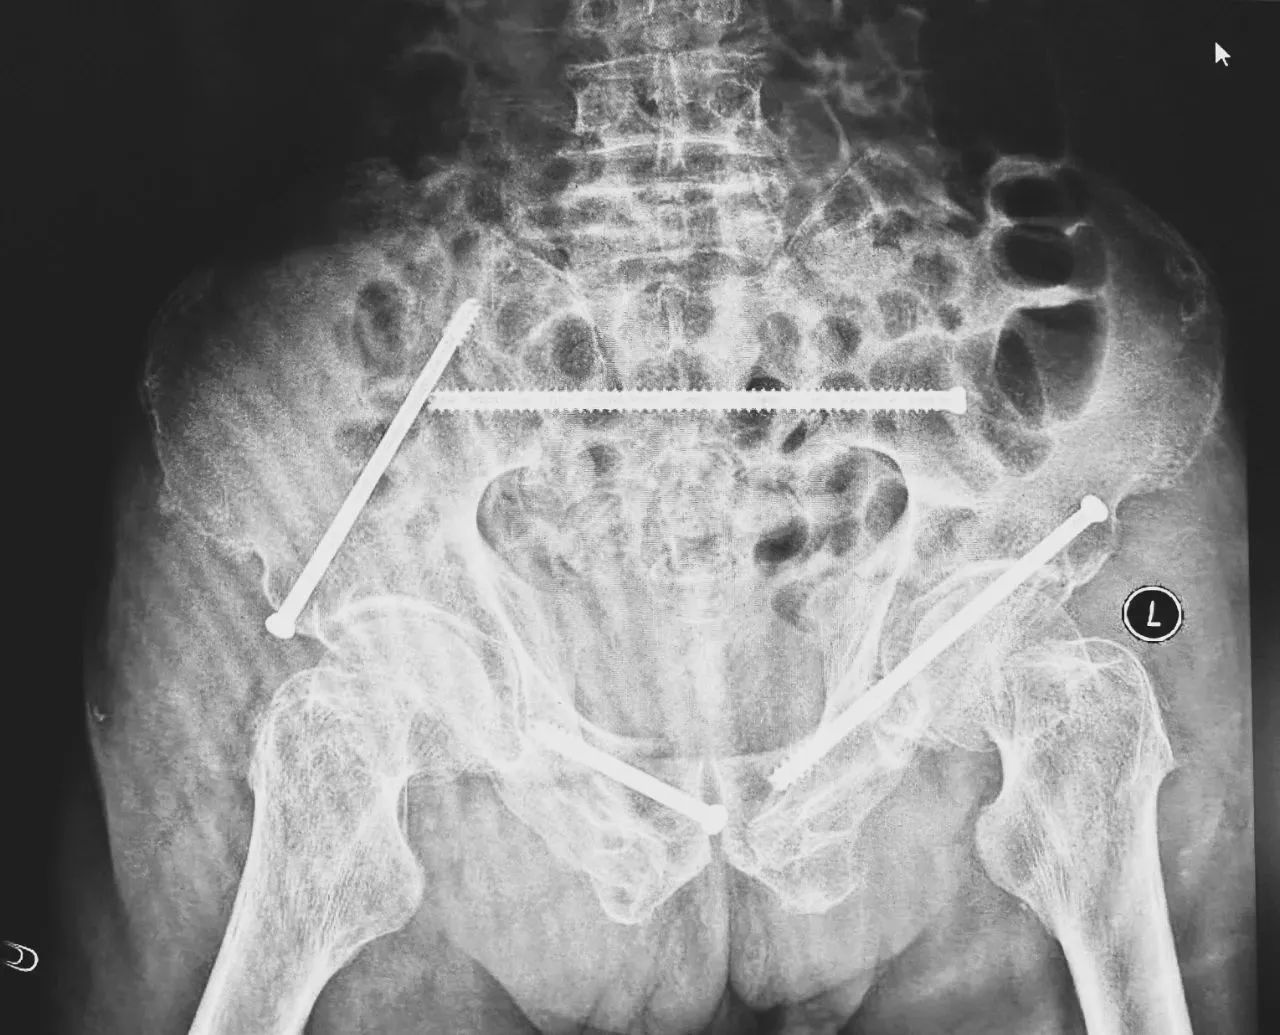

無影燈下,智能骨科團(tuán)隊(duì)將患者示蹤器,放在左側(cè)髂前上棘,使用術(shù)中三維影像設(shè)備獲取骨盆的三維圖像,掃描結(jié)果傳輸至機(jī)器人導(dǎo)航系統(tǒng),完成螺釘置入的位置和走形,并在機(jī)器人的引導(dǎo)下分別置入4枚通道螺釘。置入后再次進(jìn)行CT掃描驗(yàn)證,證實(shí)導(dǎo)針精確置入。

在骨科手術(shù)機(jī)器人毫米級(jí)精度的引導(dǎo)下,這項(xiàng)原本高難度、高風(fēng)險(xiǎn)的手術(shù)變得更加精準(zhǔn)高效。手術(shù)共計(jì)耗時(shí)1個(gè)半小時(shí),術(shù)中出血不到20毫升,每枚螺釘置入位置的切口長度約1.5厘米,完美達(dá)到了預(yù)期。術(shù)后,王大爺安全返回病房。

術(shù)后第二天,醫(yī)生團(tuán)隊(duì)復(fù)查X片顯示螺釘植入位置非常滿意,骨折基本達(dá)到穩(wěn)定復(fù)位,同時(shí),復(fù)查的全血細(xì)胞計(jì)數(shù)中,血紅蛋白指數(shù)為102g/L。術(shù)后第三天,在智能骨科病房護(hù)理團(tuán)隊(duì)及康復(fù)師的指導(dǎo)和護(hù)理下,王大爺可以坐立在床上。術(shù)后第四天,王大爺迎來了出院日,“得虧有了這么先進(jìn)的醫(yī)療技術(shù),讓我還能下地行走,謝謝你們!”

螺釘植入位置非常滿意